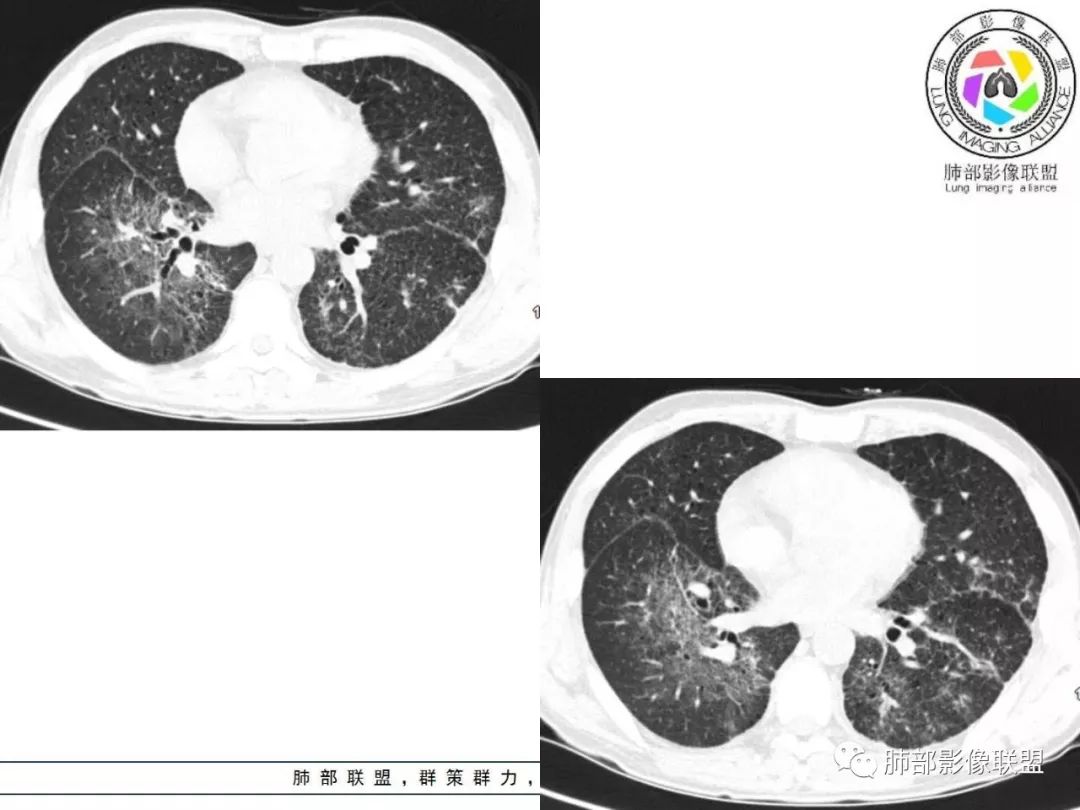

胸部CT:两肺弥漫病灶,磨玻璃影,少许实变,部分累及胸膜,磨玻璃区可见囊?少许胸腔积液,两肺可见结节,支气管血管束增粗,小叶间隔增厚,支气管走形有扭曲扩张,可见纤维化。气肿、大泡。考虑:感染性病变,PCP?查下HIV,CD4,G等。鉴别结核、结缔组织病肺浸润。

两肺弥漫性病变,沿支气管血管束分布,部分细支气管轻度扩张,两上中肺为主,部分累及胸膜下,部分磨玻璃影,部分纤维化,肺气肿肺大疱背景,胸膜增厚,少量积液,病程一月余,crp高反复发热,两肺门区增大钙化淋巴结,间质性疾病,考虑淋巴增殖性病变为主,结核可能性大,待鉴别NTM,结节病,LIP,PCP纤维化

两肺弥漫性病变,沿支气管血管束分布,部分细支气管轻度扩张,两上中肺为主,部分累及胸膜下,部分磨玻璃影,部分纤维化,肺气肿肺大疱背景,胸膜增厚,少量积液,考虑结核可能性大,鉴别op、LIP,PCP纤维化

中老年男性,发热时间长,有高热,血沉不快,双肺弥漫性病变,多发网格、结节、斑片状实变影及磨玻璃影,胸膜下、中轴间质及小叶间隔增厚,支气管血管束增粗、变形,牵拉性支气管扩张,叶间裂及小叶间隔增厚,第一考虑弥漫性间质病变,炎症?结核?结节病?综合考虑,结核排前面,多形态,病程长,间质增厚明显,较一般感染硬结感强。不确定的地方在,病灶范围广,间质累及严重,而且病人高热。其次考虑感染,或特殊菌感染。结节病不除外。

病灶呈片状磨玻璃密度影,呈典型的烟花征。磨玻璃影密度偏高,有网结节样改变,与正常肺实质分界清楚,且常见相对高密度的勾画。

病变一般沿血管支气管束分布或小叶分布,一般上肺多于下肺(这与常见继发性肺结核分布相若)。

常会伴有其他继发性肺结核病灶,如斑片影、结节影,树芽征,新旧不等改变。

2. 肺气肿背景(小叶中心性肺气肿);双肺多发病灶整体沿血管支气管束及胸膜下分布,以上叶及下叶背段分布为主,有实变及GGO,边界清楚,有树芽,小叶间隔及中央间质增厚,叶间裂见到多发结节,部分支气管不规则牵拉扩张,提示病灶纤维化明显,结合临床病史,考虑病灶为间质性感染,肺门及纵隔内有钙化淋巴结,小叶间隔结节,考虑淋巴道增值性疾病可能,综合常规要怀疑间质性肺结核。

3. 该病例临床提示感染,有支气管扩张,提示纤维化,需要与感染后的OP鉴别,但是OP病灶常无结节感;间质性肺结核有时与不典型结节病鉴别也比较困难,结节病常以双肺门淋巴结增大为特征。临床上结核发病率较高。